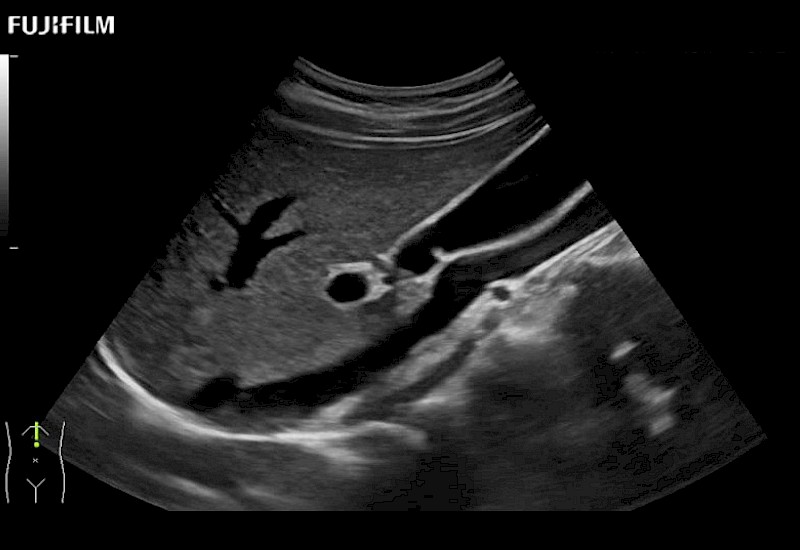

for use during open and laparoscopic procedures: Tumor localization & staging, Ablation, Resection, Biopsy, Transplant, Abdominal exploration, Robotic surgery

Curved array deep penetration “T” style finger-grip transducer for open surgical procedures.

Curved array 4-way laparoscopic transducer for better visualization of targeted lesions.